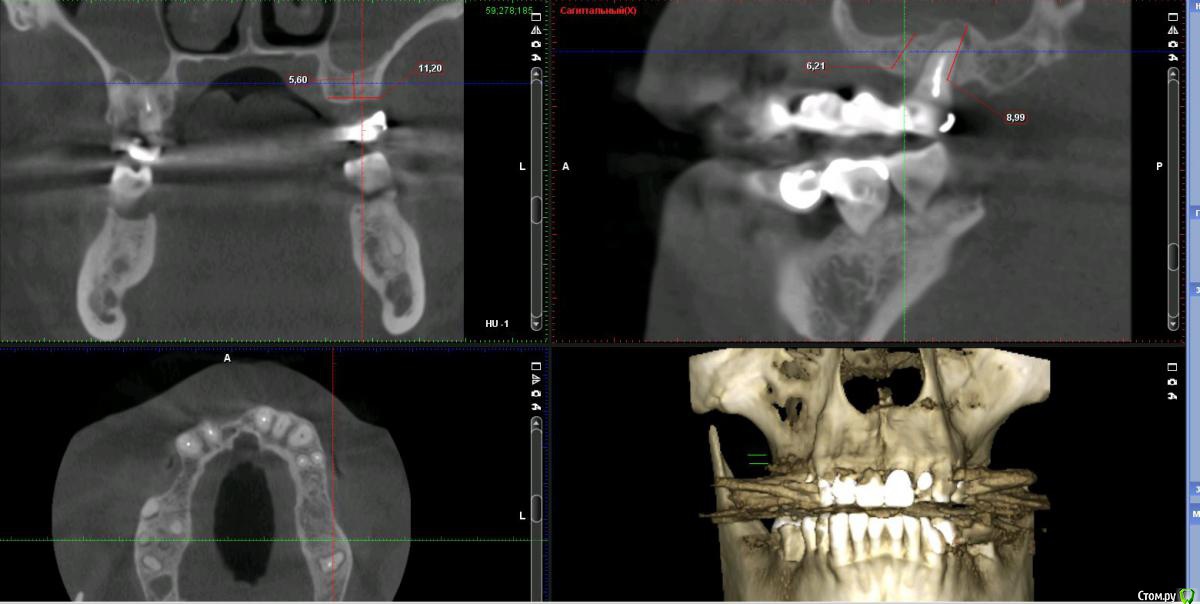

Дмитрий Л. Опубликовано 16 ноября, 2018 Поделиться Опубликовано 16 ноября, 2018 (изменено) Здравствуйте всем)Ситуация такая: старый мост 24-28. 28 симптоматичен, пациент принимает аб и противовосп. Имеется: - 24 перирадикулярные изменения (асимптомно)- 28 перирадикулярные изменения (обострение)- утолщение слизистой гайморовой (асимптомно)- невозможность имплантации в обл 26 (высота кости не позволяет) Пожелания пациента:- удаление 28 - желание сохранить мост - имплантация - нежелание носить съемную конструкцию Как планирую я:- перелечить 24, кальций 2-6 мес.- удалить 28- изготовить съёмник- выждать 4-6 мес. Повторить КТ, оценить гайморовую- имплантация 25, имплантация "где-то в обл 27" - всеми силами избежать синуса Мои грёзы:1. Ставить вблизи 24 - риск. Нужно лечить 24... реэндо... долго... может удалить? 2. Я верю, что причина хр гайморита - 28. Так ли это? Стоит ли ожидать позитивной динамики? 3. На сколько уйдёт кость после удаления 28 за 4-6 мес.? Её и так мало... Станет ли меньше? Графтить 28 не хочу. Там микробы. 4. Объём кости в обл 27-28 требует коротышку. Первыми приходят на ум Штрауман 6 мм (4 мм в кости, станет красиво) или ЭниРидж (бикортакально, скорее всего в пазуху на 1-2 мм). Нюанс в том, что я не работал этими системами... И коротышки не ставил. В общем придётся искать наборы, но это мои проблемы. 5. Итоговая конструкция: мост 25-27. При чём 27 имеет длину 4-6 мм, не слишком ли короткая дистальная опора? Вот спланировал приблизительно так... Надеюсь на отклик. Изменено 16 ноября, 2018 пользователем Дмитрий Л. Ссылка на комментарий

Дмитрий Л. Опубликовано 16 ноября, 2018 Автор Поделиться Опубликовано 16 ноября, 2018 (изменено) Bier, вы в целом согласны с планом идти отстрочено?Отметили, на сколько утолщена слизистая? Стучали бы по такой?) Irouil, предлагаете- перелечить 24, кальций 2-6 мес.- удалить 28- изготовить съёмник- выждать 4-6 мес. Повторить КТ, оценить гайморовую ?Или вы бы планировали синус в обл 26 тоже? Спасибо за комментарии. p.s. Это ведь сосуд? Изменено 16 ноября, 2018 пользователем Дмитрий Л. Ссылка на комментарий